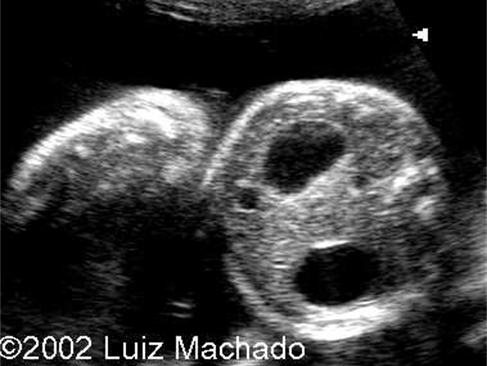

hydronephrosis